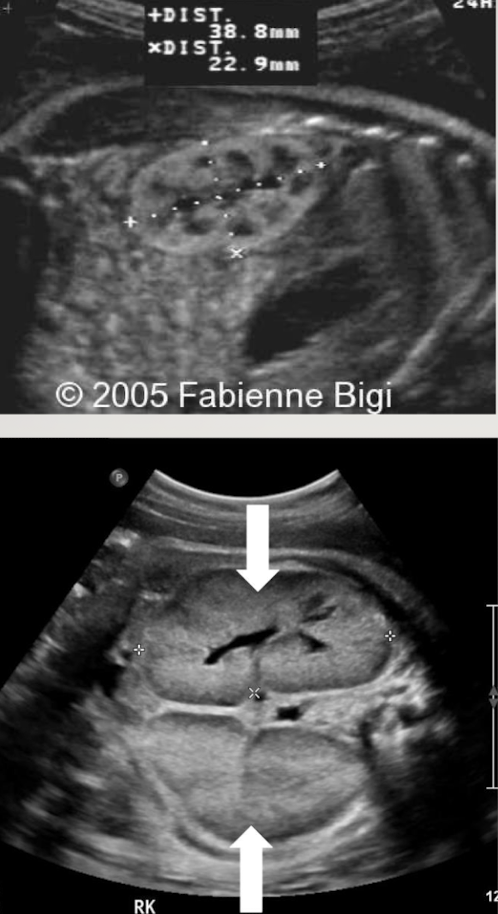

what is the pathology?

ARPKD (autosomal recessive polycystic kidney disease)